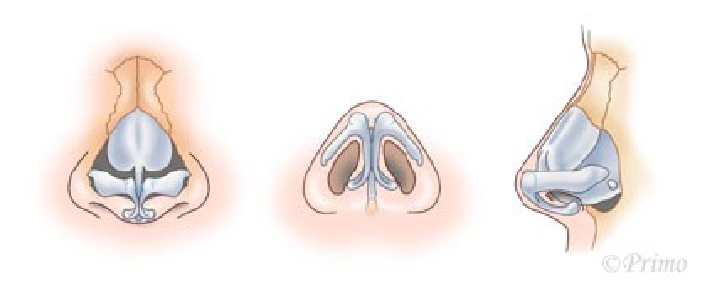

鼻の美しさの基準として鼻翼-鼻柱関係ACR(alar-columellar relationship)という指標があります。

ACRとは左右の小鼻の付け根を結んだ線を底辺、鼻柱を頂点としてできる三角形の位置関係のことで、この形が下向きの二等辺三角形であることが理想的とされています。

反対に鼻柱基部が鼻翼基部より頭側に位置する状態は、鼻柱後退(retracted columella)と呼ばれ、美容的に良好な形態とは言えません。

鼻中隔延長術により鼻柱をしっかりと降ろすことで小鼻の位置が相対的に上がり、ACRを改善させることができます。

小鼻の位置や形態を整える施術は他にも複数あり、患者様の鼻の状態、ご希望にあわせて適切な施術方法を選択することで、自然な仕上がりを実現いたします。

鼻孔縁のボリュームが大きく小鼻が垂れ下がっている方には鼻孔縁挙上術が適応になります。

反対に鼻孔縁が薄く鼻の穴が見えやすい方には鼻孔縁形成術が適応になります。

鼻翼が大きく横に張り出している方には鼻翼縮小術が適応になります。

鼻翼基部自体が下垂している方には鼻翼挙上術が適応になります。